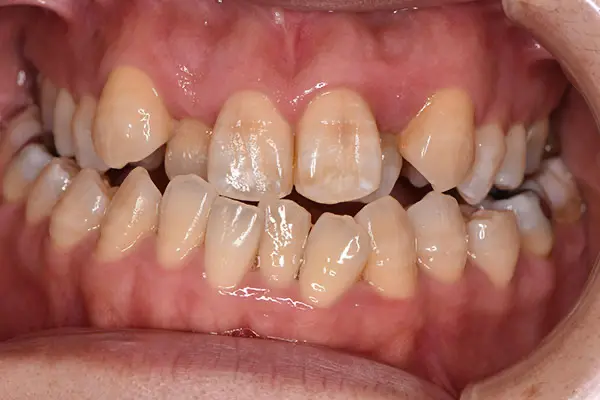

叢生・反対咬合

術前正面

術中正面

術後正面

術前上顎

| 主訴 | 歯のでこぼこ |

|---|---|

| 診断名あるいは主な症状 | 叢生、反対咬合 |

| 初診年齢 | 45歳 |

| 治療内容・装置 | マルチブラケット装置(上下表側からの矯正治療) MSE2 |

| 抜歯・非抜歯 | 下顎左第二小臼歯抜歯 |

| 治療期間 | 2年9ヶ月 |

| 費用 | 882,700円(税込) |

| 治療のリスク・副作用 | 歯の移動に伴う痛み 上下顎前歯部の歯根吸収 装置による口内炎 ブラッシング不良によるむし歯、歯周炎 |